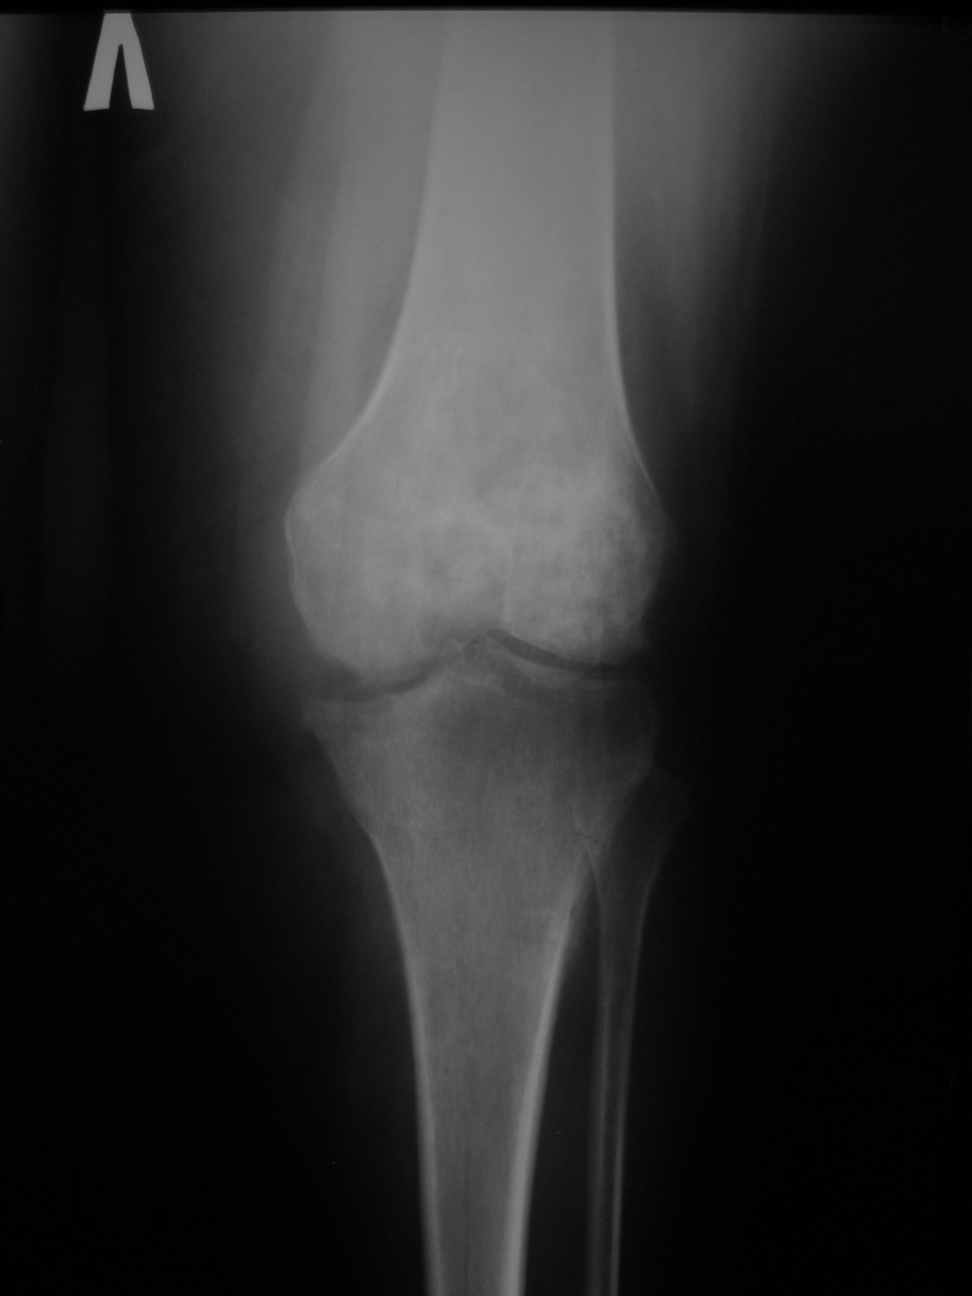

В госпиталь переведена женщина, врач, 1970 года рождения, 110 кг. 26.10.2009 г. в левый коленный сустав однократно введен Дипроспан по поводу деформирующего артроза. 02.11.2009 развился гнойный гонит. Полость сустава дренирована, проточно-промывное дренирование, наложен спице-стержневой КДА. Развился остеомиелит бедра и голени. Демонтирован КДА. По стихании гнойного процесса и заживлении ран начато реабилитационное лечение.

При поступлении к нам: Ходит на костылях с дозированной нагрузкой на левую ногу. На передней поверхности бедра и голени втянутые рубцы от спиц и стержней без признаков воспаления. Левый коленный сустав деформирован, вальгусная установка, разгибание 175 градусов, сгибание 120, движения болезненны. Надколенник фиксирован. При вальгусной нагрузке резкая болезненность. Осевая нагрузка безболезненна. При ходьбе - чувство нестабильности и боль по наружной поверхности сустава. Трофических и неврологических расстройств на конечности нет.

По нашему мнению, возможности эндопротезирования на настоящий момент, учитывая наличие остеомиелита, нет. Показано ли артродезирование?

Как вариант рассматривается артродез длинным гвоздем с цементной муфтой и антибиотиками.

Если все же готовить больную для протезирования в отдаленном периоде, целесообразно ли выполнить артроскопический артролиз в ближайшее время для восстановления амплитуды движений в коленном суставе? Можно ли ожидать спонтанного анкилоза при опорной нагрузке без операций?